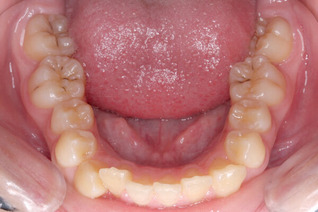

次の患者さんは顎を包むように左側全体に手があたるような頬杖でした。

下の歯は前歯までの広い範囲がへこんでいます。